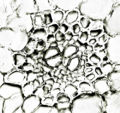

内部形態:鏡検

生姜(ショウキョウ、乾生姜)

JP15:内部形態についての記載はない。

- 生薬の性状

本品は偏圧した不規則な塊状でしばしば分枝する。分枝した各部はやや湾曲した卵形又は長卵形を呈し、長さ2~4cm、径1~2cmである。外面は灰白色~淡灰褐色で、しばしば白粉を付けている。折面はやや繊維性、粉性で、淡黄褐色を呈する。横切面をルーぺ視するとき、皮層と中心柱は明瞭に区別され、その全面に維管束及び分泌物が暗褐色の細点として散在する。 本品は特異なにおいがあり、味は極めて辛い。

- 産地による比較

| 生姜 <中国雲南省> | 生姜 <中国貴州省> | 生姜 <日本> | 生姜 <インド> |

|

|

|

|

| 維管束 | 維管束 | 維管束 | 維管束 |

|

|

|

|